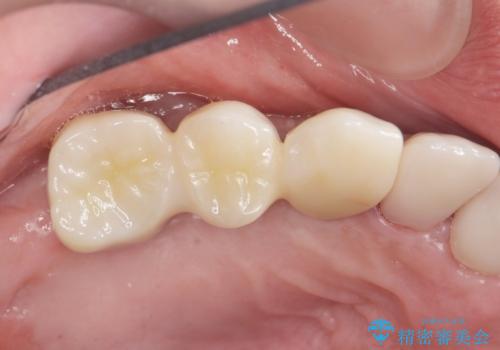

しっかりと咬むことができるようになり、喜んで頂けました。

他院ではお断りされたインプラント治療を行うことができ、ご満足頂けました。

インプラントの種類:ストローマン BLT

被せ物の種類:オールセラミッククラウン ベレッツァ